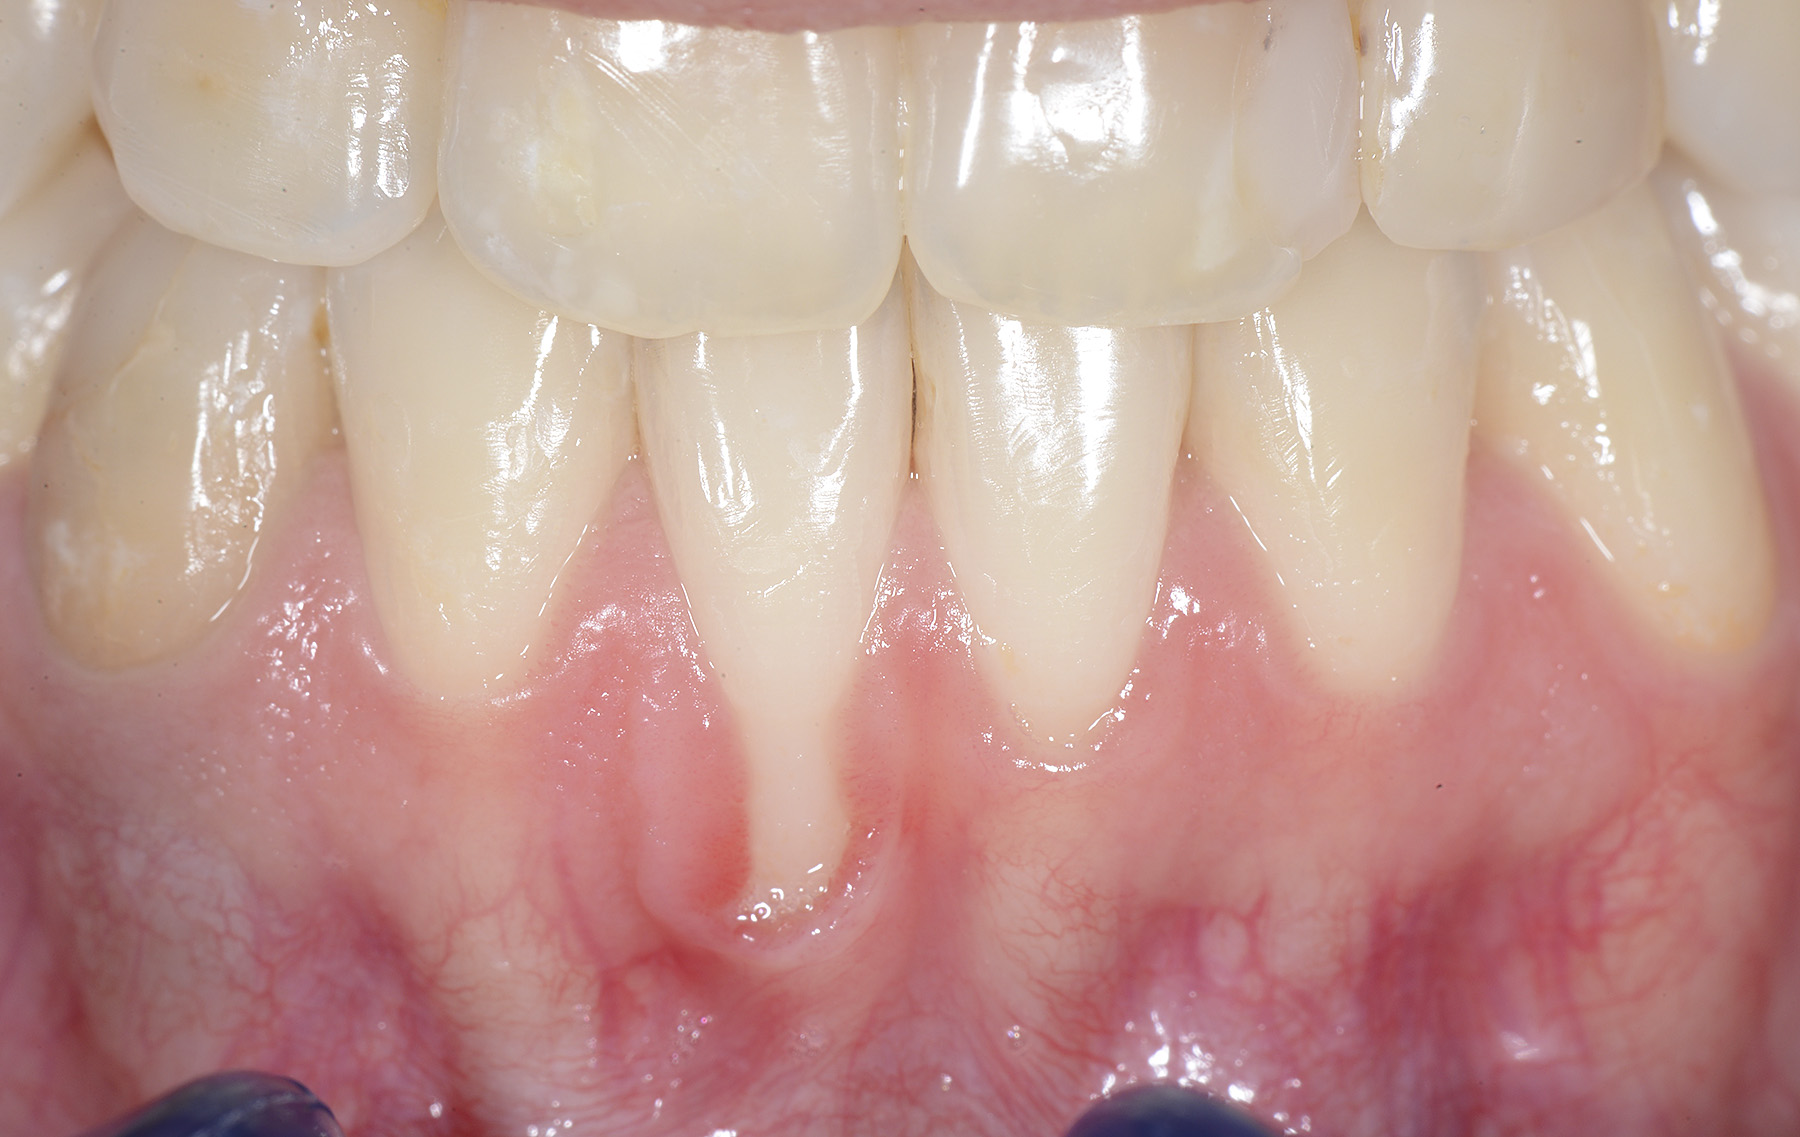

PREMESSA: in seguito all’estrazione dell’incisivo laterale superiore di destra, resasi necessaria per cause batteriche, si decide di affrontare il caso con il posizionamento di un impianto in sostituzione dell’elemento mancante dopo guarigione del sito infetto. Con tecniche rigenerative sia dei tessuti ossei mancanti a causa dell’infezione pregressa, sia dei tessuti gengivali che appaiono inizialmente troppo spostati in alto, si ripristina una corretta morfologia delle parabole (contorni) gengivali e delle papille interdentali (triangoli di gengiva tra due denti vicini).

Vengono utilizzati 2 tipi di provvisori: il primo, cementato ai denti vicini, viene utilizzato dal momento dell’estrazione del dente fino ad impianto osteointegrato (circa 6 mesi); il secondo, avvitato direttamente all’impianto, ha una funzione di prova estetica ma soprattutto di guida per la maturazione dei tessuti gengivali peri-implantari portandoli verso la maturazione completa prima di posizionare la corona finale in disilicato di litio.